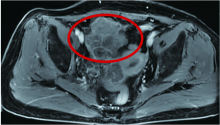

杨洪娟, 孙云川, 何新颖, 毕建强, 肖丽.子宫内膜中肾样腺癌1例并文献复习[J]. 国际肿瘤学杂志, 2023, 50(4): 255-256. |